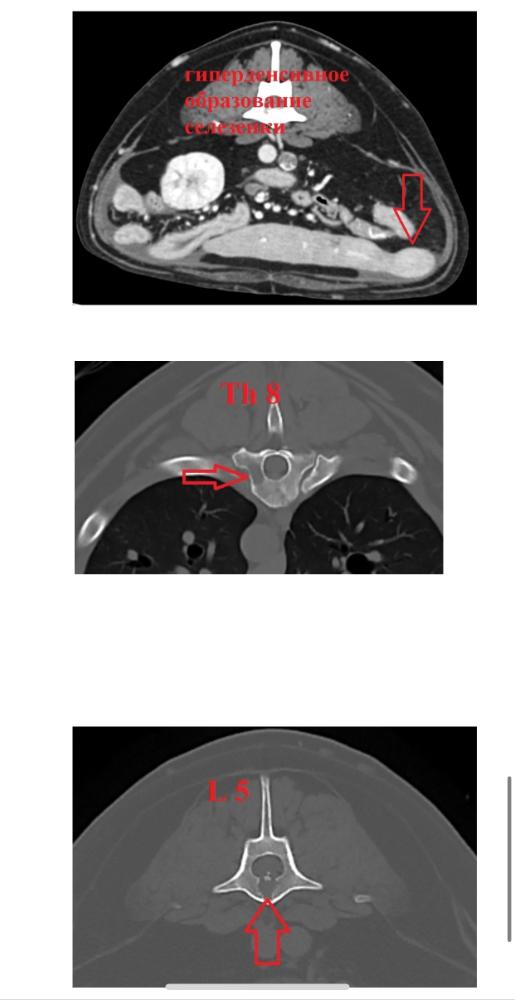

Дорогие форумчане, с Вилли случилась беда!!!🆘

Вилли разбил инсульт, 23.02 мальчик встал на кровати, пошатываясь, попытался спрыгнуть, но потерял сознание и нырнул в бессознательном состоянии на пол, тывнувшись носом с этой высоты в пол ((( Выбито 4 зуба. Сделали еще УЗИ - нашли образования в надпочечнике и печени, еще разные вопросы. 😔 Целый букет!

Сейчас мальчик был на КТ, ждем результаты. Когда падал с кровати без сознания, сломал об пол 4 зуба. Удалили их под седацией сейчас, поскольку давать полноценный наркоз чревато. Теперь надо обращаться к терапевтам за грамотной терапией, чтобы поддержать ребенка на сколько возможно. Там букет, боюсь, что на КТ откроется еще более страшная картина.

Получили описание  КТ и свежие анализы крови 😔 Множество образований, показатели крови ухудшаются...